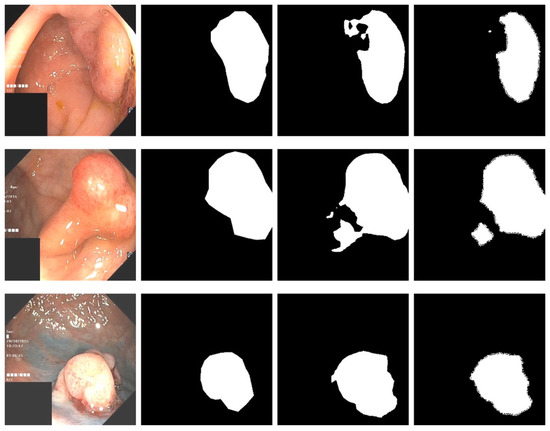

There are currently only a few public datasets of intestinal polyps available for model training and testing. Polyps exist in various shapes and colors as well as textures [11]. As shown in Figure 1, the minute difference between polyps and the normal ambient environment or partially diseased areas covering the feces is the main challenge in the detection of polyps. In this paper, we used the open datasets of Kvasir-SEG [12] and CVC-ClinicDB and performed relevant experiments

Figure 1.

An example of polyp pictures from the Kvasir-SEG dataset, together with their accompanying masks. The first and third columns show the original image; the second and fourth columns show the accompanying masks.

For the polyp image segmentation task, every pixel in the training image was labeled as either polyp or non-polyp. The evaluation of the PRAPNet was accomplished utilizing the Kvasir-SEG dataset and CVC-ClinicDB [17] dataset. The Kvasir-SEG dataset consists of 1000 polyp images and their corresponding mask maps annotated by specialist endoscopists from Oslo University Hospital, Norway. The CVC-ClinicDB dataset consists of 612 polyp images. Figure 1 shows example images from the Kvasir-SEG dataset and their corresponding templates. As the number of polyp pictures was too small, direct training would lead to overfitting. Thus, it was necessary to increase the number of polyp pictures in the training set; the number of Kvasir-SEG images was 11,000 and the number of CVC-ClinicDB images was 6732. Traditional data enhancement technology—namely, vertical flip, horizontal flip, 90 degrees clockwise rotation, translation, changing the image brightness, and Gaussian blur—was used to increase the training samples from the initial images. Of these images, 80% were randomly selected for the training, 10% were used for the validation, and 10% were used for the testing.